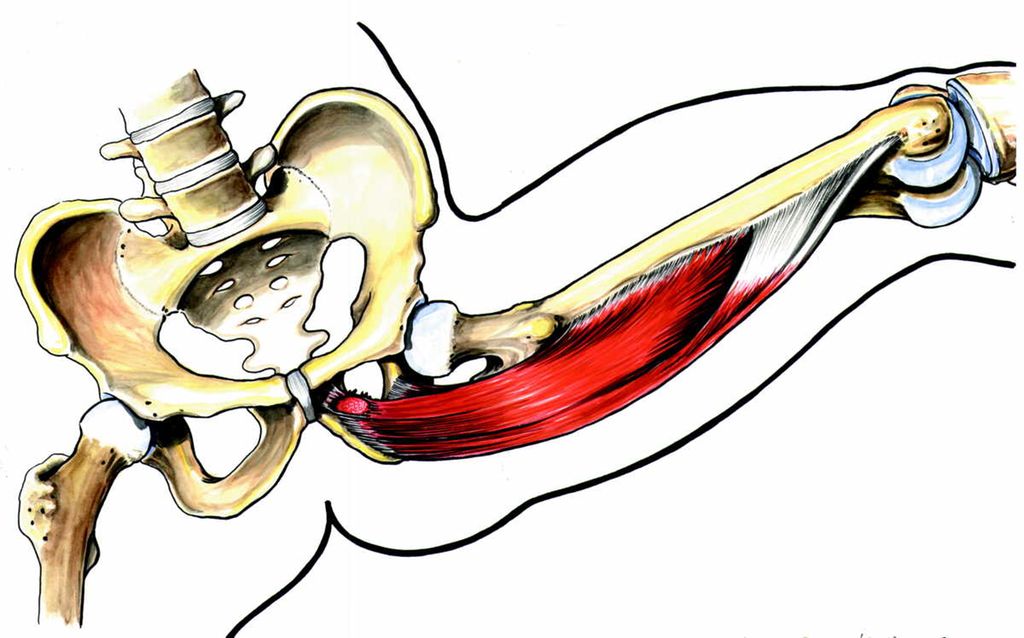

Hamstringstrekk

Strekkskader i lår er svært vanlige i idretter som fotball, håndball, bandy og ishockey. Disse skadene oppstår særlig i de såkalte hamstringmusklene på baksiden av låret. Som regel oppstår de i forbindelse med «eksplosive» spurtløp. Hamstringstrekk er derfor den vanligste skaden blant sprintere.

Også blant fotballspillere er hamstringstrekk den vanligste skaden. Det gjelder både på elitenivå og på amatør- og skolenivå. Om lag en firedel av alle akutte skader er en hamstringstrekk. Slike strekk kan ta lang tid å lege, og har vi først fått skaden én gang, er det lett å få den igjen senere på samme sted.